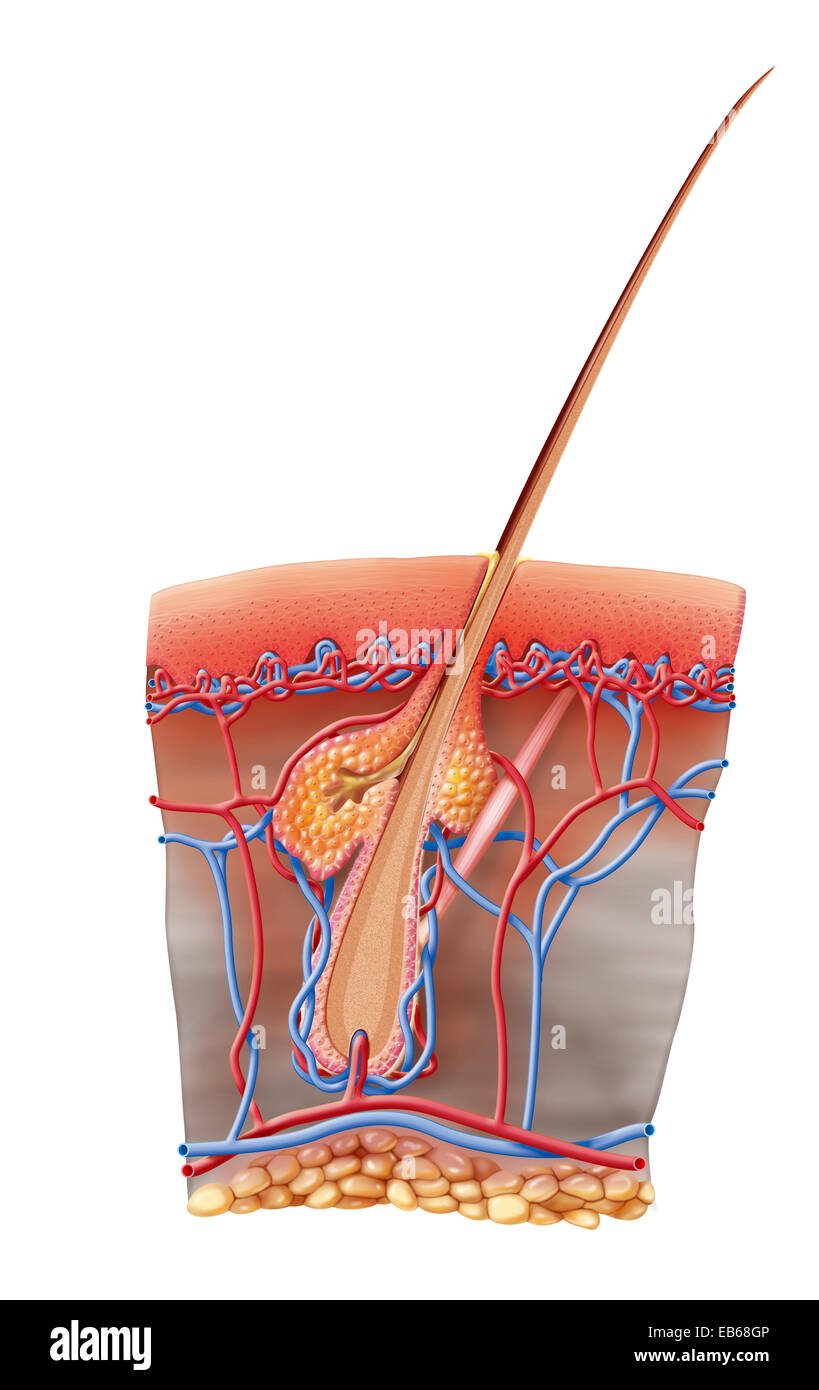

ERYTHEMA ILLUSTRATION Stock Photohttps://www.alamy.com/image-license-details/?v=1https://www.alamy.com/stock-photo-erythema-illustration-75741142.html

ERYTHEMA ILLUSTRATION Stock Photohttps://www.alamy.com/image-license-details/?v=1https://www.alamy.com/stock-photo-erythema-illustration-75741142.htmlRMEB68GP–ERYTHEMA ILLUSTRATION